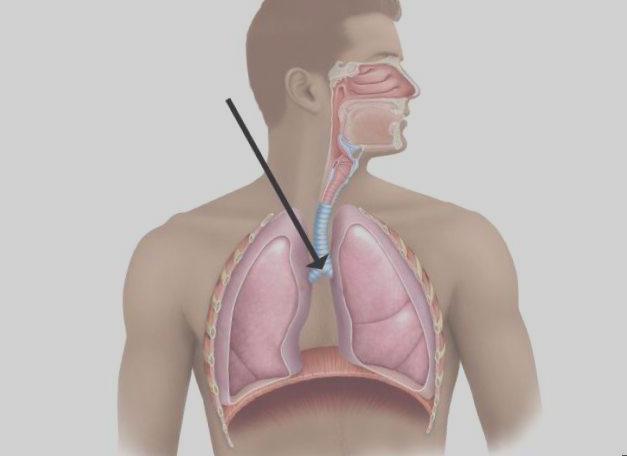

Фотографии и информация о бронхоскопии при туберкулезе